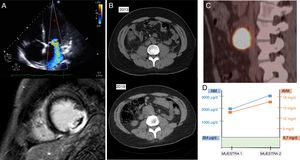

A su llegada, el paciente presentaba tendencia a la hipertensión (190/90mmHg) y taquicardia (130lpm), con elevación del segmento ST septal <1mm en el electrocardiograma. Presentaba cardiomegalia en la radiografía de tórax y elevación de troponina I, leucocitosis y neutrofilia en la analítica sanguínea. El ecocardiograma mostró hipocinesia difusa y dilatación del ventrículo izquierdo con insuficiencia mitral grave y fracción de eyección del ventrículo izquierdo del 15%. La sospecha inicial fue de miocarditis infecciosa, por el antecedente de una picadura de garrapata. En la resonancia magnética cardiaca se observó realce tardío sugestivo de necrosis y un trombo apical (fig. 1). Pese al inicio de la anticoagulación, presentó un ictus isquémico cardioembólico por el que se trasladó a nuestro centro para realización de trombectomía mecánica y completar el estudio cardiológico.

Algoritmo diagnóstico de la disfunción ventricular grave por feocromocitoma. A) Miocardiopatía dilatada de novo con insuficiencia mitral funcional grave. Además, en la resonancia magnética cardiaca se observa el realce tardío compatible con infarto. B) Crecimiento de la masa retroperitoneal. C) Tomografía por emisión de positrones. D) Niveles de las metanefrinas.

Se realizó una coronariografía que fue normal, y se sospechó un infarto embólico. Por ello, tras 2 tomografías computarizadas craneales de control, se reintrodujo la anticoagulación una semana después. Debido a fiebre persistente sin foco claro, se solicitó una tomografía por emisión de positrones que mostró una masa retroperitoneal de 42×42×47mm con intenso hipermetabolismo patológico (fig. 1), ya presente, aunque de menor tamaño, en una tomografía computarizada realizada en 2013 por pancreatitis, que determinó catecolaminas negativa en ese momento. Todos los estudios microbiológicos fueron negativos.

Durante la dosificación de fármacos bloqueadores beta, presentó shock cardiogénico con deterioro de la fracción de eyección del ventrículo izquierdo que precisó inotrópicos. Con estos hallazgos y teniendo en cuenta el comportamiento hemodinámico con los bloqueadores beta, se realizaron 2 determinaciones de catecolaminas urinarias cuyo resultado fue más de 4 veces los valores normales, lo que confirmó el diagnóstico: paraganglioma secretor de normetanefrina y noradrenalina (fig. 1). Además, apareció elevado el ácido vanilmandélico, dato específico de esta entidad.